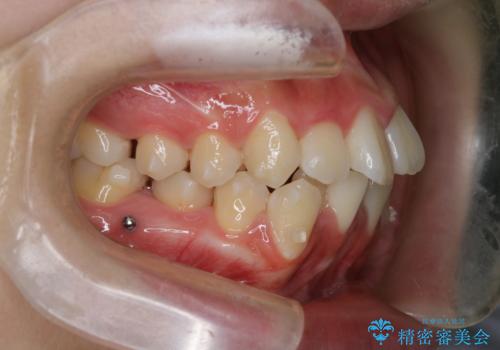

【インビザライン】前歯の凸凹を非抜歯で治療

- 前歯の凸凹を主訴の来院されました。

奥歯を後ろの方に移動させるために矯正用のアンカースクリューを使いながら治療をおこないました。

患者さんの都合により、マウスピースの装着時間が不足したため、途中からワイヤーにて治療を行いました。